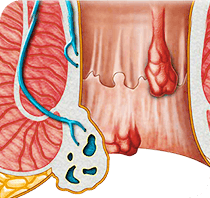

Da fervente sostenitrice dell'innovazione, ha notato il gel

Proctowell in una conferenza a Barcellona. Ad oggi, non ho visto

una selezione di principi attivi più efficace. Il gel contiene

una vasta gamma di componenti biologicamente attivi che

completano e migliorano l'azione reciproca. A differenza di

molti altri prodotti, Il gel a base naturale è completamente

sicuro e non causa allergie. Lo consiglio a tutti i miei

pazienti che hanno problemi di emorroidi.